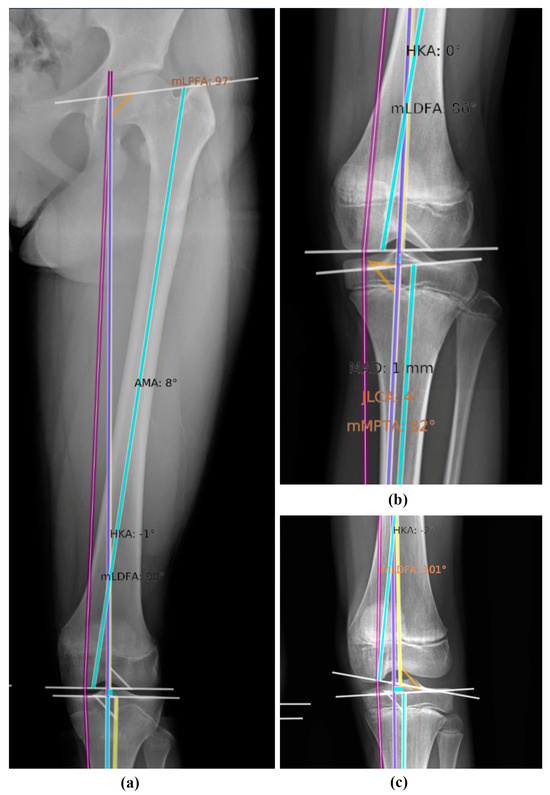

| Measurement Variables | Description | Landmarks Used | |

| Femur length | Distance between the most superior point of the femoral head and the most distal point of the medial femur condyle | 1 and 2 | |

| Tibia length | Distance between the most distal point of the medial femoral condyle and mid-tibial roof | 2 and 3 | |

| Full leg length | Distance between the most superior point of the femoral head and mid-tibial roof | 1 and 3 | |

| Leg length discrepancy | Difference between the full leg lengths of both legs within the same patient | 1 and 3 | |

| mMPTA | Angle between the mechanical tibial axis and proximal tibial knee joint orientation line | 4 and 5 | |

| mLDFA | Angle between the mechanical femoral axis and the distal femoral joint orientation line | 6 and 7 | |

| HKA | Angle between the mechanical femoral and tibial axes | 6 and 4 | |